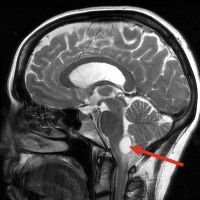

Hipertensão Intracraniana Idiopática/Pseudotumor

A hipertensão intracraniana idiopática (HII)/Pseudotumor é o aumento da pressão no crânio. Ocorre...